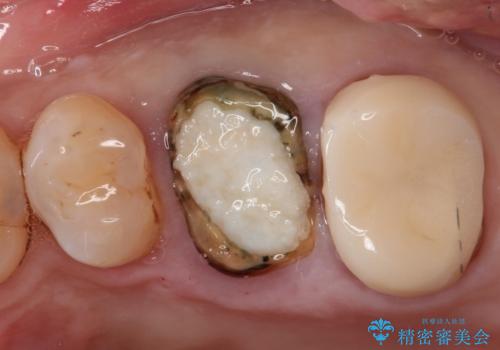

【歯牙破折】インプラントによる咬合回復

- 痛みを主訴に来院されました。

歯牙の破折を認めたため抜歯をし、インプラントにて咬合回復をしました。

抜歯後、骨増生を行ったのちインプラントを埋入しています。